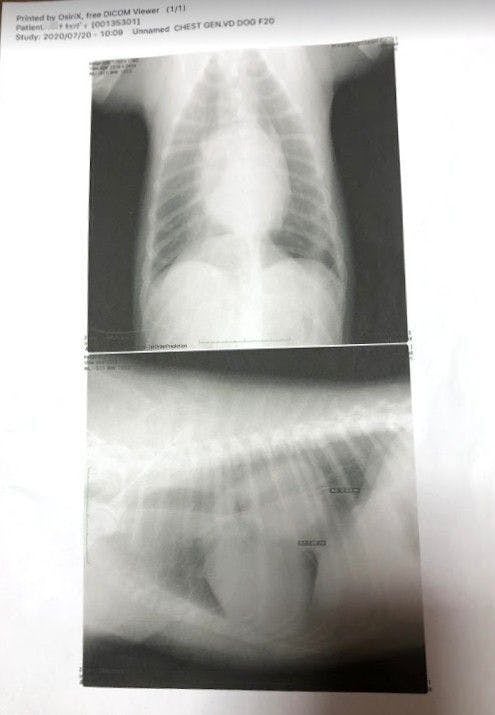

しかし大学病院で検査するには、前の検査(年末の検査)から半年も経っていたため、再度血液検査とレントゲン検査をしてみたところ、とてもショックな結果が出ました。。。(2020年7月)

これだけだとよくわからないと思うので、昨年末に撮ったレントゲン写真と並べてみました。

腫瘍の大きさが2倍以上になっていたのです(泣)

これだけ腫瘍が大きくなっているのを見て、先生の診断は

「手術で腫瘍を取り除けるかと以前は思っていたが、これは難しいかもしれないです。やれるとするならば、放射線治療をするか、薬を飲んで小さくするかという治療になるかもしれません。」

「腫瘍が心臓を圧迫していて左の肺を押しつぶしている為(右肺のみの呼吸)、通常の半分の呼吸しか出来ていず、少し歩くだけでもすぐに苦しくなる状態です。」